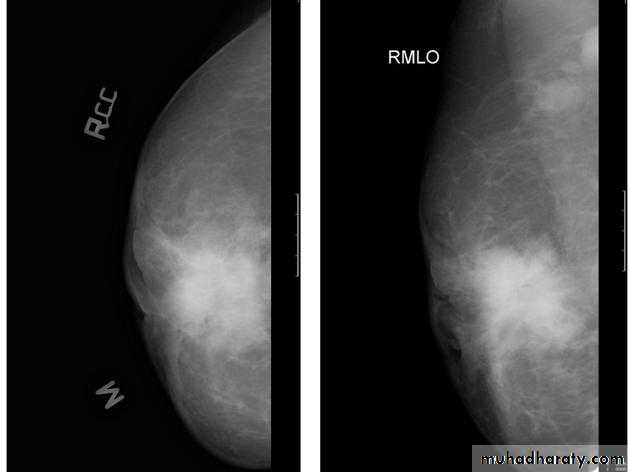

A…..Invasive ductal carcinoma is a subset of ductal carcinoma. It is an infiltrating, malignant and abnormal proliferation of neoplastic cells in the breast tissues. It is the most frequently seen breast malignancy .Radiographic features

Mammogramspiculated hyperdense lesion

oval/lobulated lesion

microcalicifications